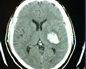

Científicos afirman que el ACV tiene tratamiento

¿Por qué? Debido a que el ACV puede tratarse efectivamente, aunque cuando esto no ocurre con la celeridad y la experiencia requerida, un tercio de quienes lo padecen fallece –se estima que a nivel mundial 17 millones de personas sufrieron un ACV en 2015- y el mismo porcentaje queda con discapacidad permanente (pérdida de visión, del habla, parálisis y confusión, entre otras). De hecho el ACV es globalmente la 2ª causa de muerte y la 1ª de discapacidad.

En cuanto a las técnicas, una de ellas es el tratamiento endovascular o cateterismo del ACV, que recibió la máxima recomendación posible (clase 1, con nivel A de evidencia) para ser utilizada en ciertos pacientes. “Es la primera vez que este tipo de tratamiento se recomienda enfáticamente para el ataque cerebral, dado que nuevos estudios mostraron con suma claridad que es beneficioso en ciertos grupos de pacientes”, refirió Lylyk.